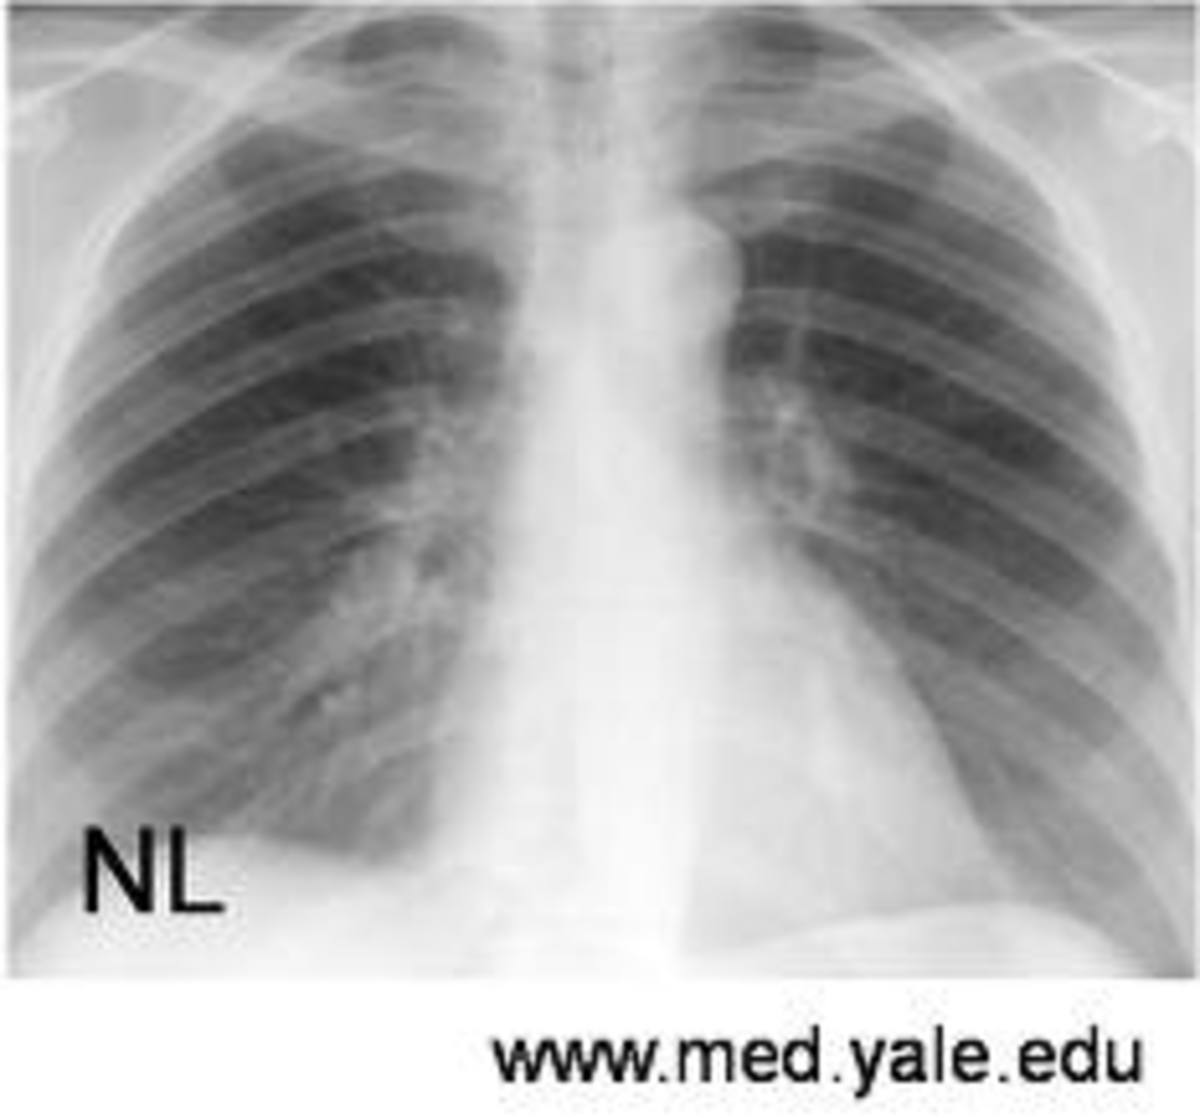

From ar.inspiredpencil.com

Emphysema Lung Vs Normal Lung What Do Your Lungs Look Like With Emphysema See a healthcare provider for a diagnosis. This can cause a condition called cor pulmonale, in which a. the primary symptom of chronic bronchitis is mucus production, including a wet cough that produces thick, discolored (yellow,. emphysema is a lung condition. emphysema is a chronic obstructive pulmonary disease that causes symptoms like coughing, wheezing, and breathing difficulties.. What Do Your Lungs Look Like With Emphysema.